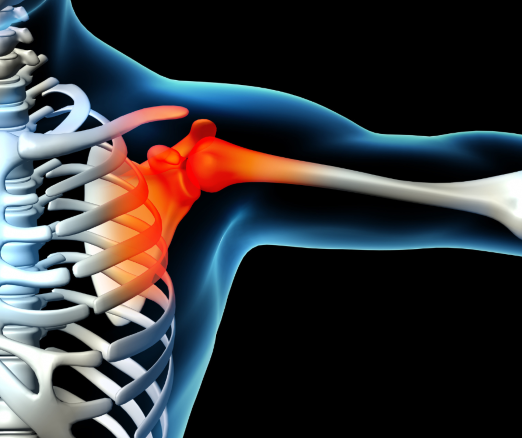

Bark to kompleks kilku stawów, kości oraz odpowiednich struktur. W jego skład wchodzą kość ramienna, łopatka i obojczyk, stawy: ramienny, barkowo-obojczykowy, mostkowo-obojczykowy, łopatkowo-żebrowy. Wszystkiemu towarzyszą ścięgna, mięśnie, więzadła i kaletki. Budowa barku jest skomplikowana, dzięki czemu umożliwia duży zakres ruchu. Charakterystyczne dla kompleksu barkowego jest to, że często pomimo występowania jakiś dolegliwości, można wykonywać zamierzone ruchy. Przykładowo, jeżeli chcemy podnieść rękę do góry, to osiągniemy to wykorzystując do tego inne struktury anatomiczne. Tym sposobem można doprowadzić do przeciążenia, które pogorszą jego stan.